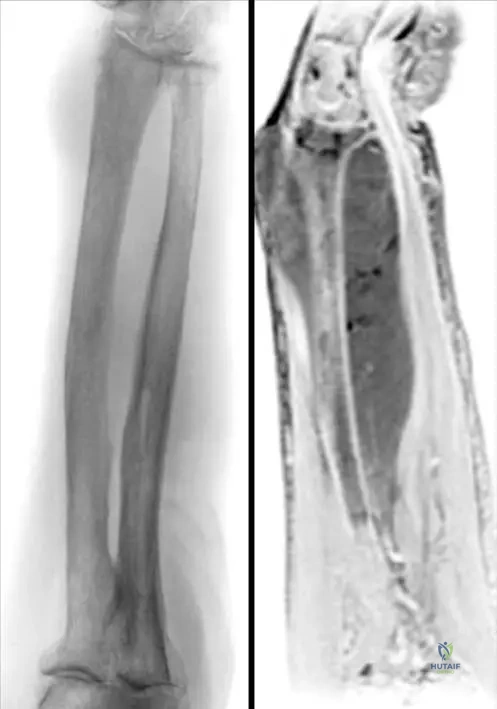

Rationale: Fig. 8.108 and its caption describe "Lymphoma involving left forearm. Characteristically there is a soft tissue mass with minimal roenterographic changes (a). The MR picture (b) shows the large size of the tumor." This description perfectly matches the vignette. Osteoid osteoma typically presents with a nidus and prominent reactive sclerosis, often without a large soft tissue mass. Enchondroma, non-ossifying fibroma, and fibrous cortical defect are typically intraosseous lesions with more characteristic radiographic appearances and do not usually present with a significant soft tissue mass.

Rationale: Fig. 8.108 and its caption describe "Lymphoma involving left forearm. Characteristically there is a soft tissue mass with minimal roenterographic changes ( a ). The MR picture ( b ) shows the large size of the tumor a b." This imaging pattern of a large soft tissue mass with subtle radiographic bone changes is highly characteristic of lymphoma. Lipoma is a benign fatty tumor, typically not associated with bone involvement or significant pain. Myositis ossificans involves heterotopic bone formation in soft tissue, which would be visible on radiographs. Ganglion cysts are benign fluid-filled sacs, and osteoid osteoma has a characteristic nidus.

Correct Answer: C